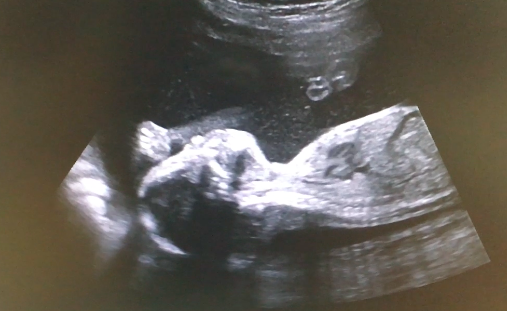

Девчонка наша развивается шикарно, опережает сроки на неделю вперед) Весит уже целых 606 грамм, зевает, чавкает и закидывает ножки к голове! По допплеру посмотрели мои артерии и пуповину - все хорошо, ох, люблю я свою матку)))))

Фотки с УЗИ и вопросы про выбор коляски под катом, вэлкам)

И ниже обещанные фотки с УЗИ) Есть еще видео, но загружать сюда сложнова-то, не стала пока